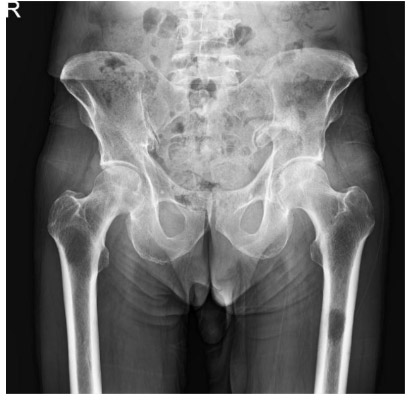

Before the surgery: The X-ray shows damage caused by metastasis in the upper region of the left hip joint and the upper parts of both femur bones.